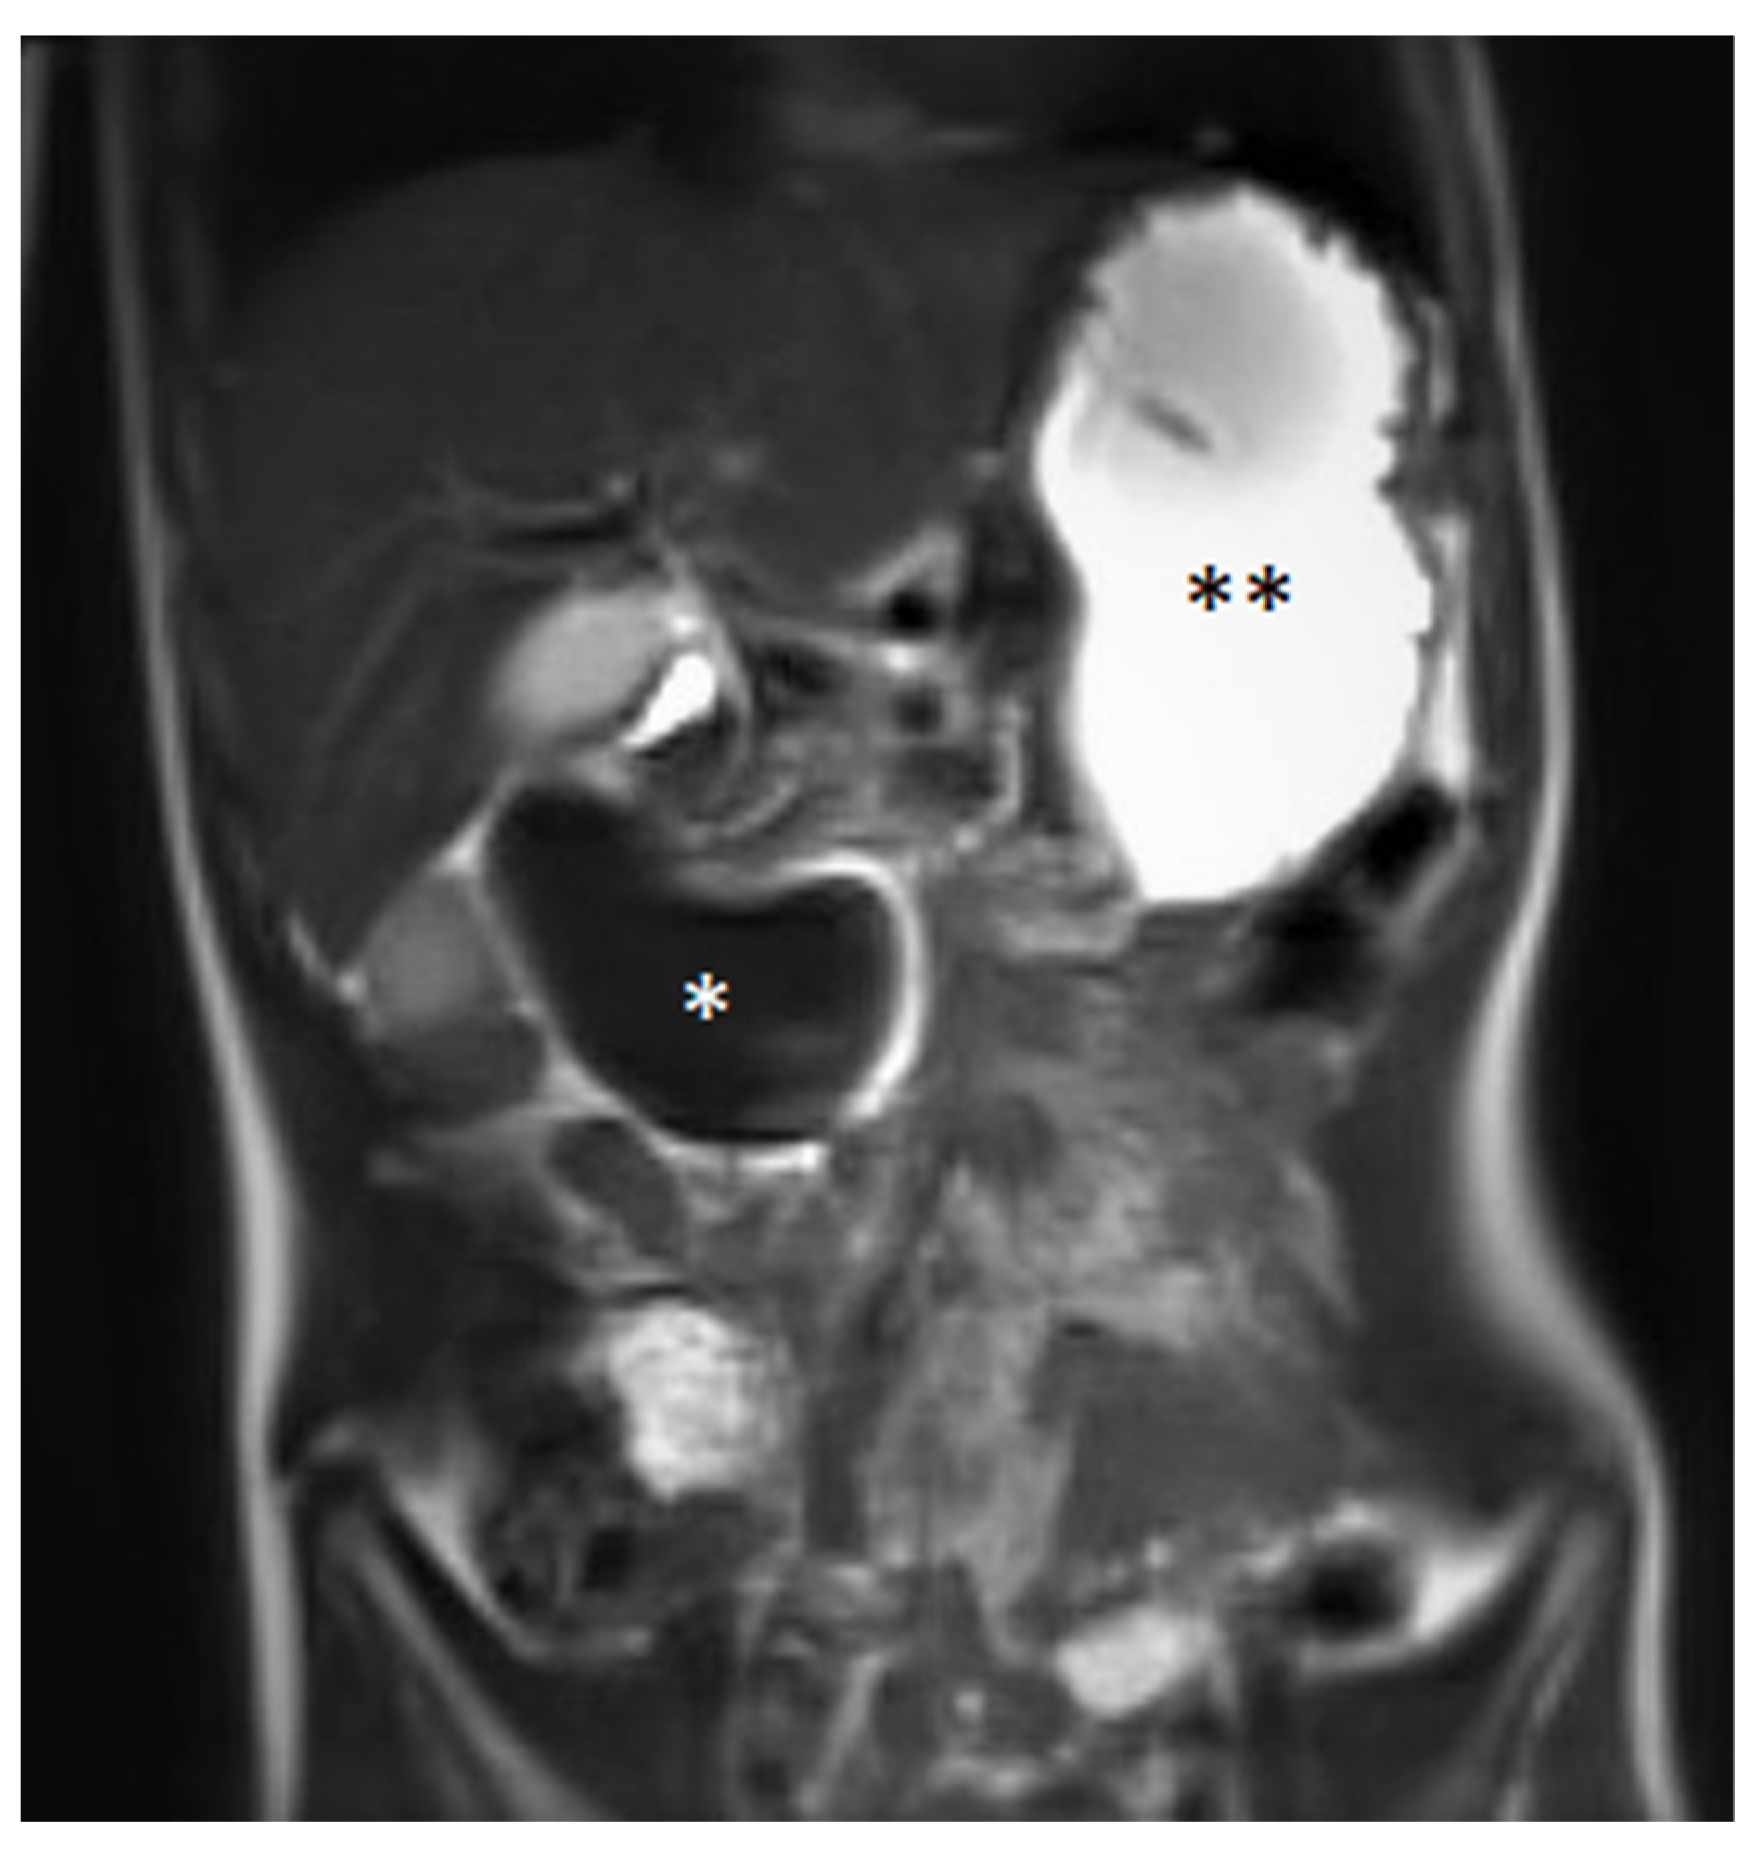

3. Case Report